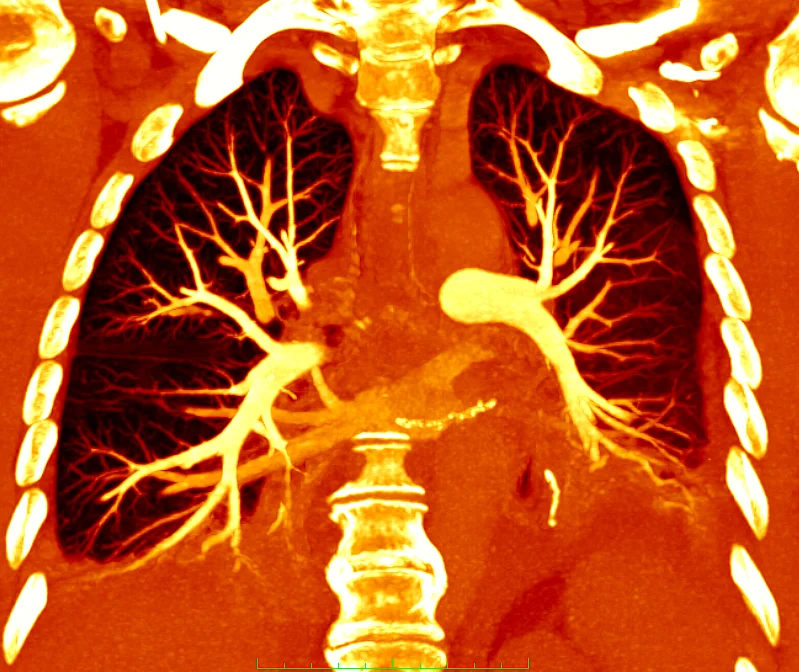

Zu den eingesetzten bildgebenden Methoden gehören neben dem Röntgen vor allem moderne Schnittbildverfahren wie die strahlenfreie Magnetresonanztomographie (MRT), die Computertomographie (CT) und der Ultraschall (Sonographie). Die Abteilung für Radiologie am AKH Celle verfügt über eine hochmoderne radiologische Geräteausstattung, die unter anderem eine routinemäßige Durchführung von radiologischen Spezialuntersuchungen wie die Untersuchung des Herzens oder der Prostata ermöglicht.

Computertomographie: Gesamtes Spektrum der CT Diagnostik

- CT Diagnostik des Halses, Brustkorbes und Bauchraumes

- CT Angiographie des gesamten Gefäßsystems

Für die CT-Diagnostik verfügt die Abteilung für Radiologie über zwei moderne Multislice Computertomographen. Es werden Spezialuntersuchungen wie die Herz-CT, Perfusions-CT oder virtuelle CT Kolonographie durchgeführt (siehe Leistungsspektrum).